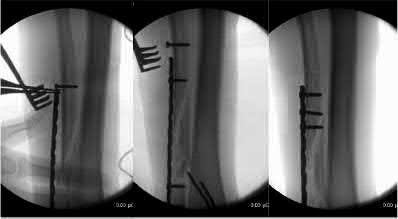

A 25-year-old male sustains an ankle fracture dislocation and undergoes open reduction and internal fixation. He returns to clinic five months following surgery complaining of continued ankle pain and instability with weight bearing. His immediate post-operative AP radiograph is seen in Figure A. Which of the following could have prevented this patient from developing persistent pain?

The patient presents with continued ankle pain and instability following open reduction and internal fixation. The radiograph in figure A demonstrates inadequate restoration of fibular length, likely leading to continued tibiotalar instability.